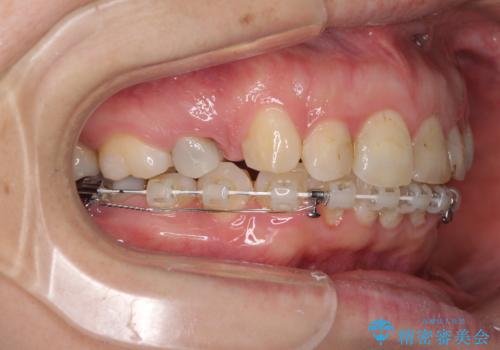

咬合力が非常に強く、スペースがなかなか閉じなかったことと、上下の正中が著しくずれてきてしまったため、下顎左側小臼歯を途中抜歯することとなりました。

歯の動きが鈍く、矯正治療だけで4年以上の期間を要することとなりました。